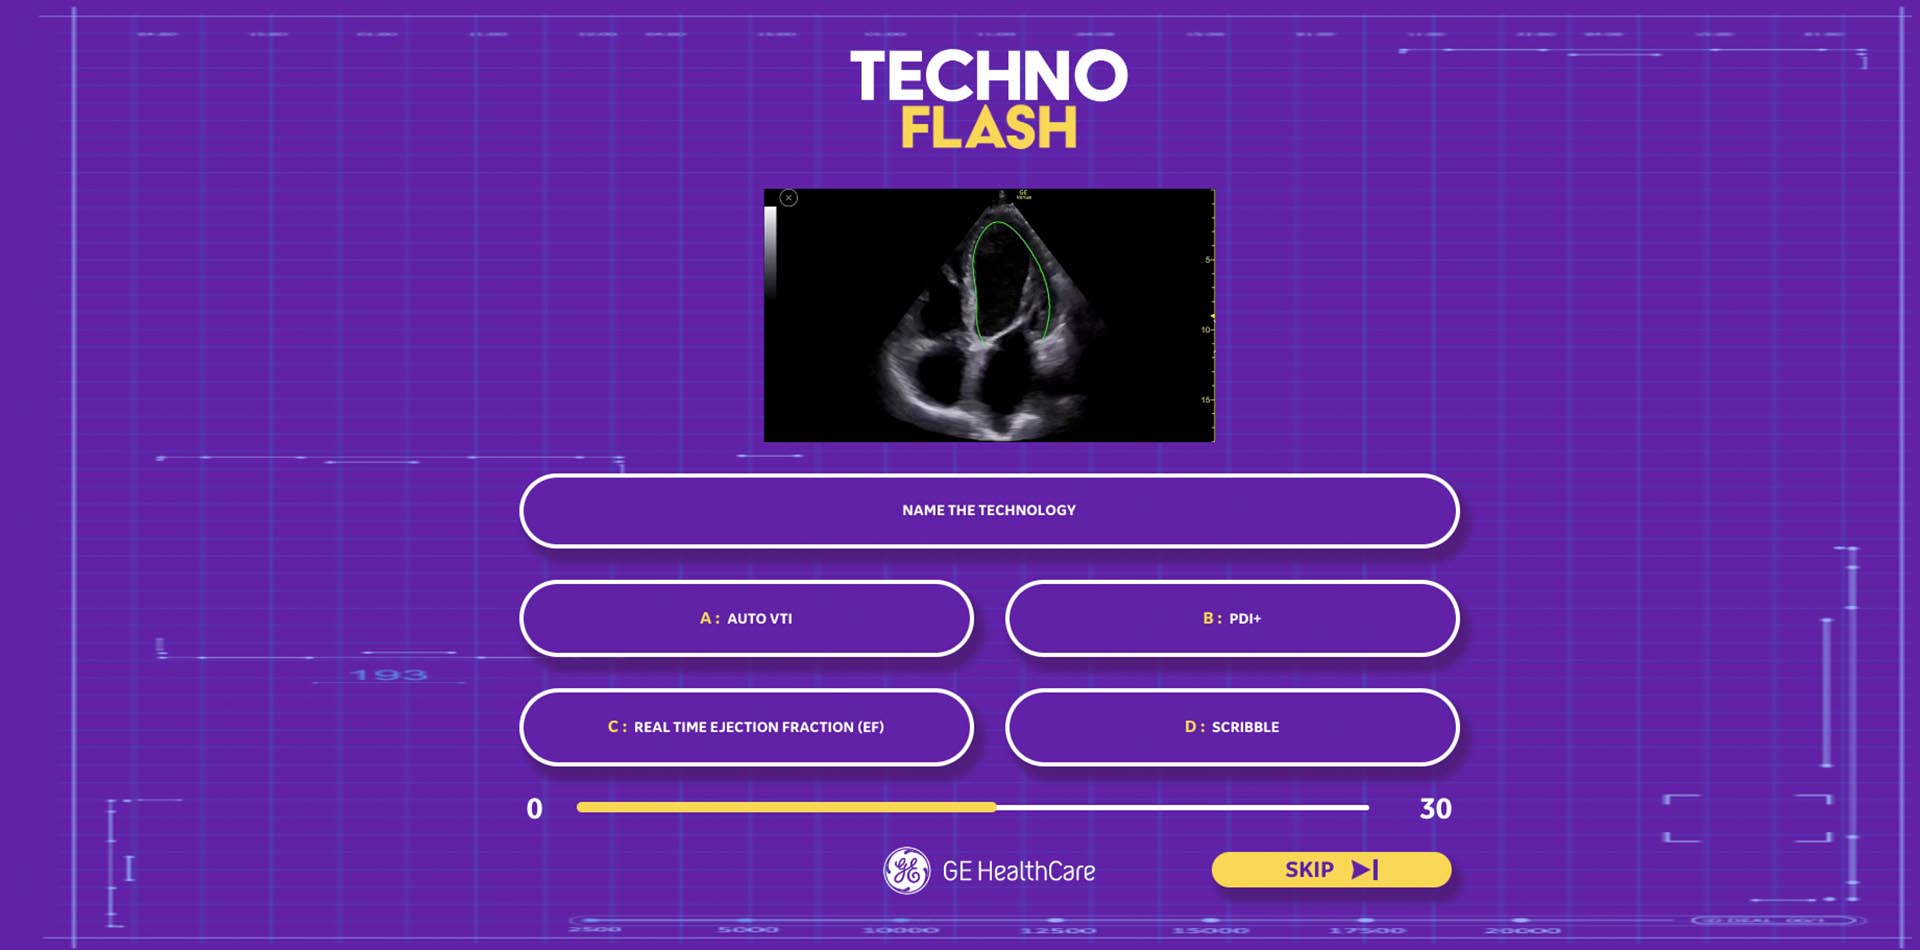

Our creative team worked to find something that would be exciting enough to attract an audience, and would work on the screens available on the stand. It was decided that new games should be developed that played into the audience’s competitive nature.

Using a combination of strategic insight and a creative ideation process, the team at TrunkBBI developed multiple game ideas, from a simple quiz to a more complex ‘Beat the AI’ concept, allowing sonographers to test their skills against a pre-programmed scan in real-time. The intent was for this to showcase the incredible power of GE HealthCare’s machine AI capability, and prove to our audience how it could help reduce scanning time in a busy role.

The concepts worked on multiple levels – continuing with GE HealthCare’s goal of highlighting new ultrasound machine updates, and as a way to engage more fully with BMUS attendees and collect information for follow-up.